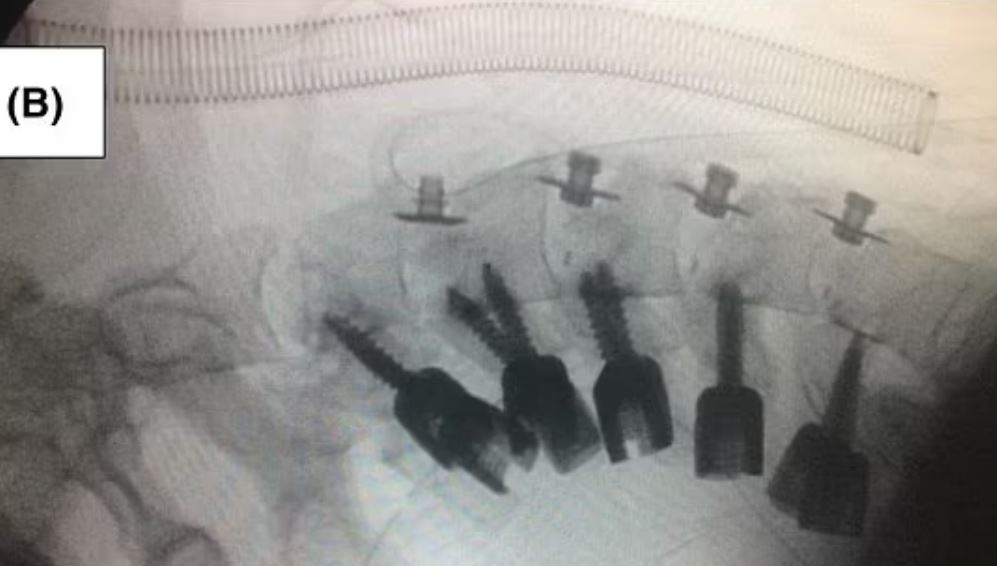

男子在尋求醫療協助前,頸部彎曲症狀已經持續15個月,已經無法靠復健矯正,因此只能進行手術。為了重新調整頸部,醫生決定切除變形的骨頭,好在男子腦神經、肌力測試與自主神經系統檢查結果全都正常,手術後恢復良好,第2天就能戴著固定器行走。而經歷這麼一遭,男子也擺脫了毒癮。

圖片來源 / 翻攝自Dailymail